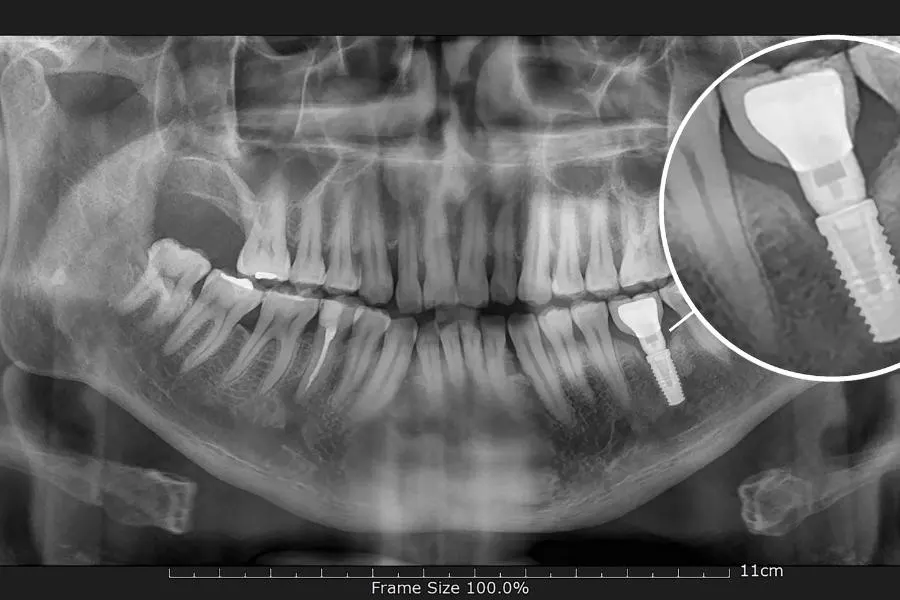

Exámenes radiográficos

Suele ser, entre todos, el más recomendado. Mediante este examen de radiografía periapical, se podrá observar el diente afectado.

Sin embargo, también se puede realizar otros tipos dependiendo de cuál sea el caso y daño generado.